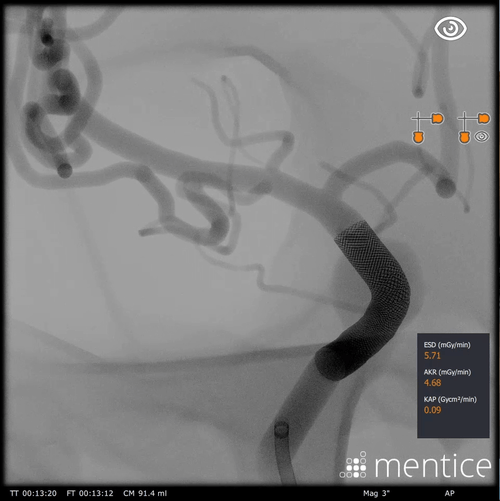

The FD cases teach specific techniques for flow diversion, focusing on the basic steps of assessing the size of the aneurysm, locating landing zones, and deploying a flow diverter using the bi-manual technique for proper push and pull for optimal deployment.

Deployment of flow diverter using bi-manual technique

Practice deployment in patient-specific anatomy